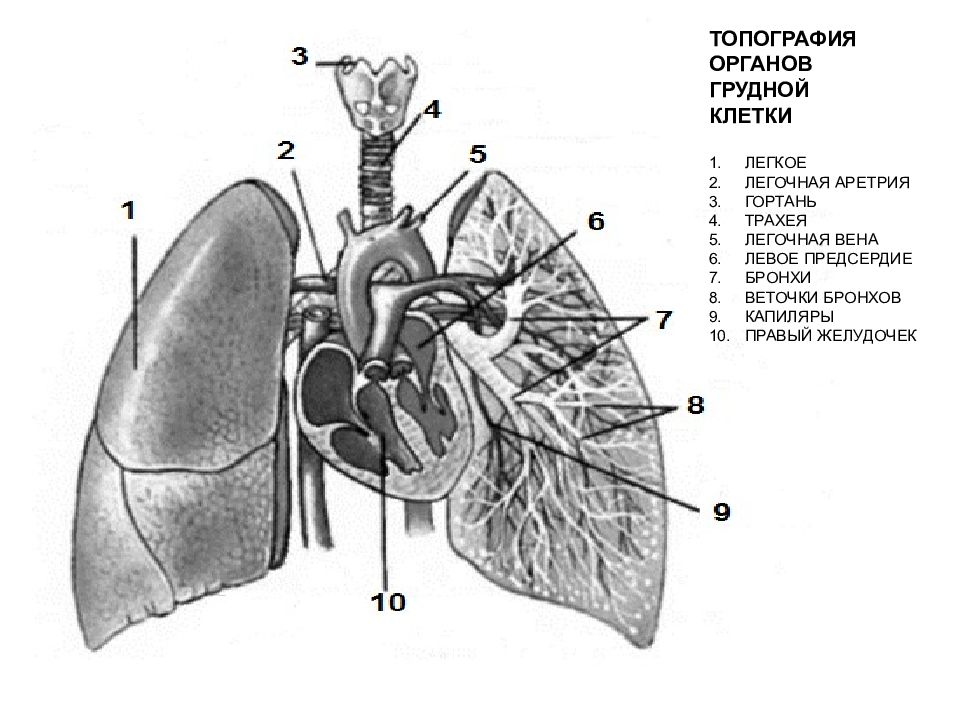

Анатомические изображения сегментов легких различных животных

Раздел: Другие животные